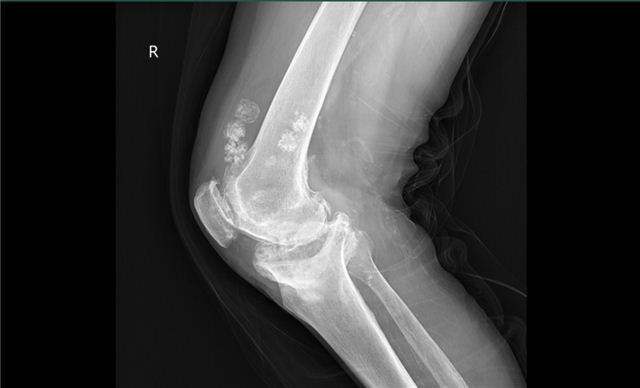

经过检查,结果提示该患者双膝重度骨关节炎,内翻畸形,内翻约20度,内侧平台塌陷约2cm。诊断很明确,双膝骨性关节炎。

术前X片